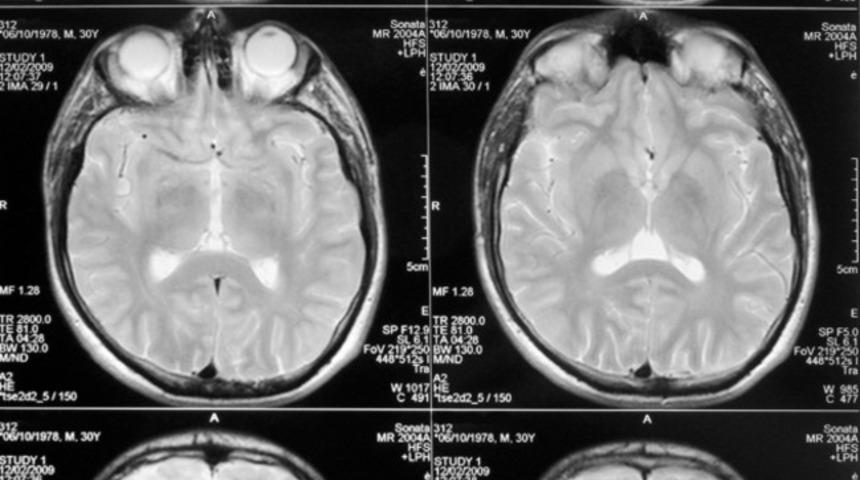

Sürekli epilepsi nöbeti geçiren 8 yaşındaki İngiliz kızı beyin ameliyatına alan doktorlar kafatasını açtıklarında gözlerine inanamadılar. Küçük kızın beyninde tam 100 tenya yumurtası vardı. Küçük kız yumurtaların çıkartılmasının ardından sağlığını yeniden kazandı.

Altı aydan sonra küçük kızın nefesi kesilmeye ve yürüyememeye başladı. Yapılan taramaların ardından minik kızın beyninde 100 tane tenya yumurtası olduğunu tespit ettiler. Beynindeki kurtçuklar çıkarıldıktan sonra küçük kız iyileşti ve yürümeye başladı.